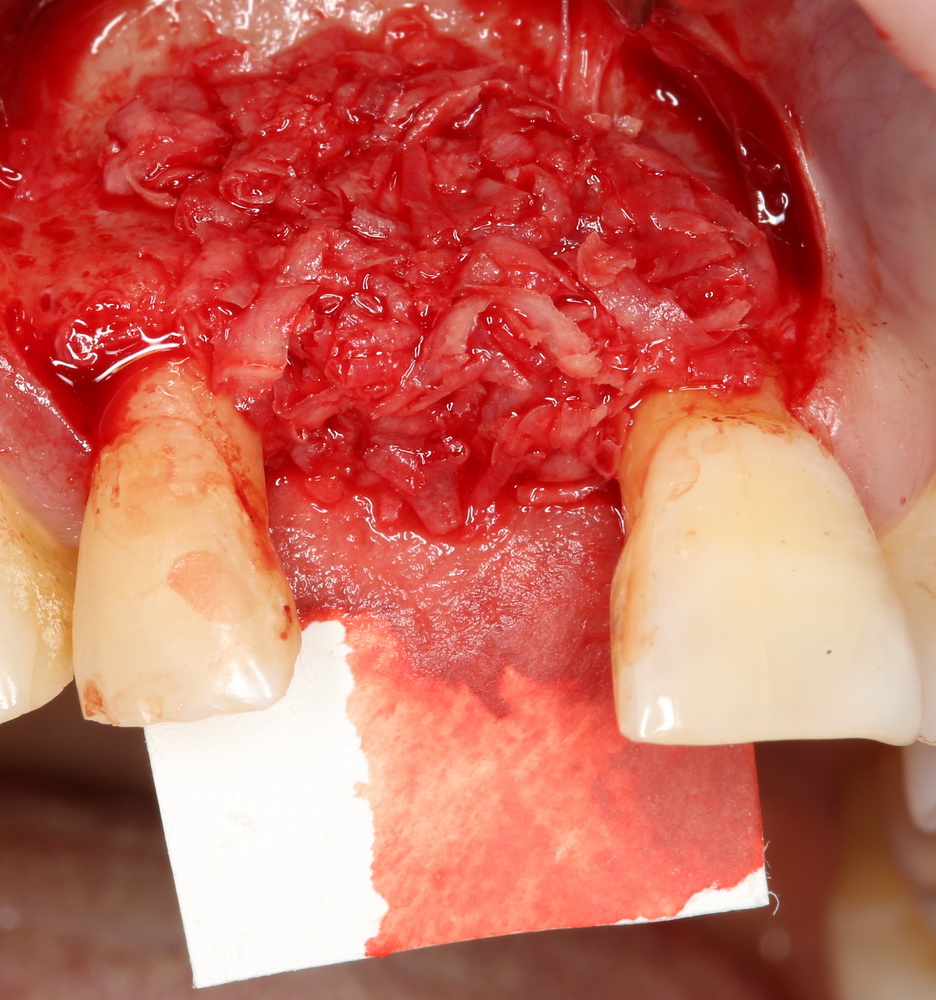

ТОЛЬКО аутокостная стружка содержит клетки, необходимые для регенерации костной ткани. Поэтому ее можно использовать как изолировано:

Так и в смеси с ксенотрансплантатами. Например, Geistlich Bioss:

Оптимальное соотношение — 50/50, но допускается и 30/70.

Например, в следующей ситуации:

Оставить так, как есть — это значит, сильно рисковать имплантом и объемом альвеолярного гребня — фактически, большая часть импланта пятого зуба «висит в воздухе». Поэтому получившуюся костную полость мы заполняем аутокостной стружкой в смеси с Bioss и закрываем коллагеновой мембраной BioGide: